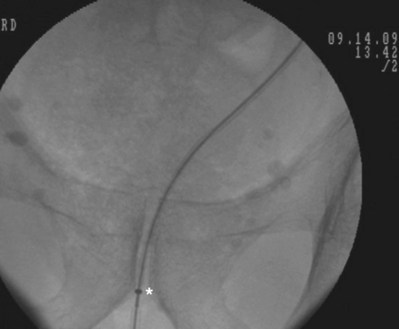

An alternative technique that relies more on fluoroscopic visualization for stent placement and less on cystoscopic visualization is often advantageous when dealing with more challenging stent placements such as impacted ureteral stones or malignant obstruction (Figs. 7-7 through 7-16).

Figure 7–7 Flexible cystoscopy is used to locate and, under fluoroscopic guidance, pass a floppy tip guidewire through the ureteral meatus.

After obtaining bladder access with either a flexible or rigid cystoscope, a floppy-tip guidewire is advanced into the ureteral meatus and coiled in the renal pelvis using fluoroscopy, the cystoscope is then removed and an 8- to 10-Fr coaxial dilator is advanced under fluoroscopy until the 10-Fr sheath is at the urethral meatus. The 8-Fr internal dilator is removed, leaving a conduit (10-Fr outer sheath) through which to advance the stent.

The ureteral stent is then advanced over the guidewire through the 10-Fr sheath by using a pusher with a small fluoroscopically visible metal band at its tip. The metal tip pusher is advanced under fluoroscopic control to the upper border of the pubic symphysis in male patients and lower border in female patients, while stabilizing the position of the lower end of the stent. The 10-Fr sheath and subsequently the guidewire are removed, allowing the stent to curl in the bladder.